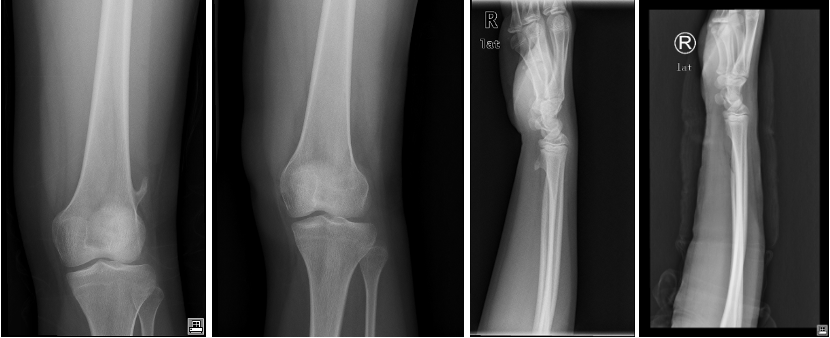

诊断方法: 骨软骨瘤的诊断主要依赖影像学检查。X线片可以显示肿瘤的骨性基底和软骨帽,而MRI则有助于评估肿瘤的软组织成分,尤其是在症状明显或疑似恶变时。CT扫描也可以提供关于肿瘤骨性结构的详细信息。